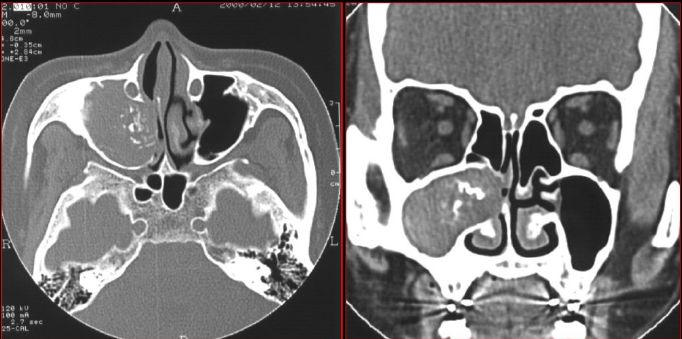

慢性多发鼻窦炎鼻息肉